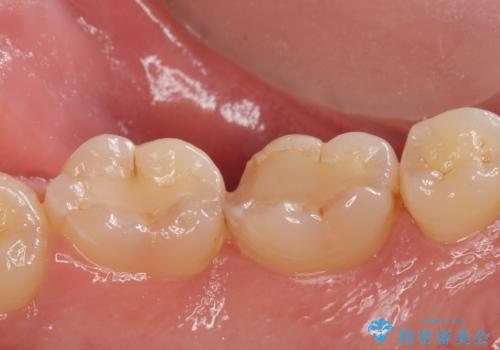

- ゴールドアンレー 11万円費用は治療当時の料金となります

今回はなるべく歯質を残したいとの事なのでゴールドの詰め物でご案内させて頂きました。ゴールドは範囲が多くても割れる心配がありません。また、虫歯の再発リスクが低いです。